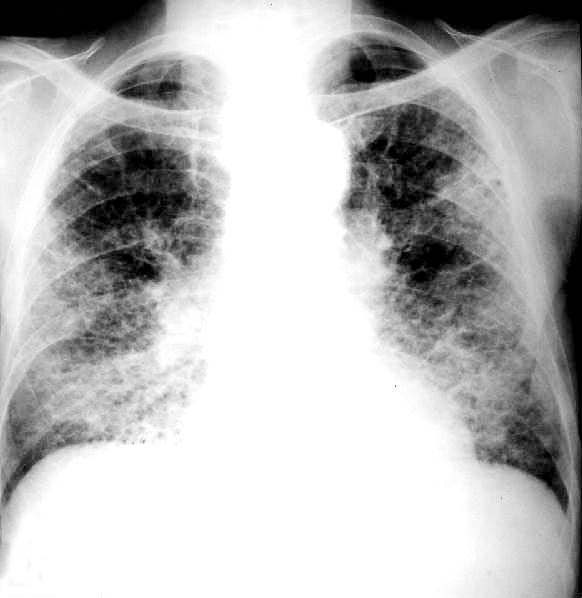

PLACA 19